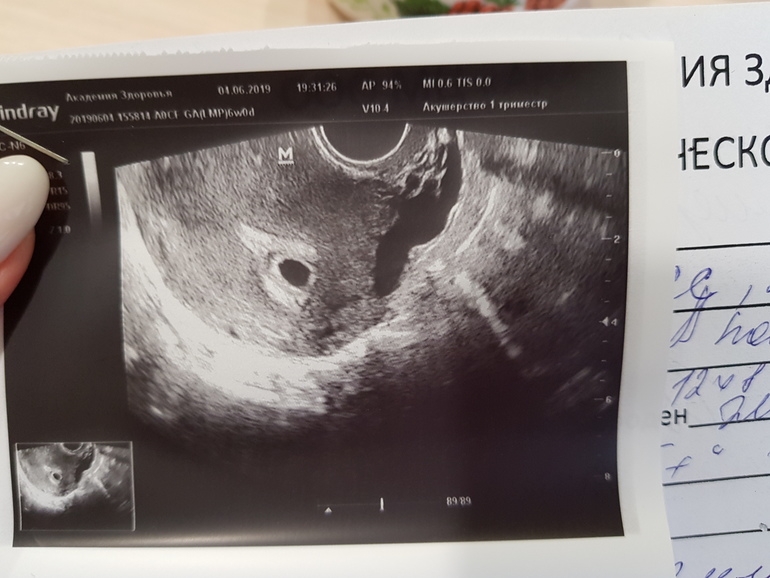

УЗИ в 6 недель (контроль для исключения ЗБ???)

Не проходите мимо, пожалуйста 🙏🙏🙏 нужна ваша поддержка или совет. Была на УЗИ неделю назад (5+0 нед) - нашли только ПЯ 3 мм. Сегодня пошла на УЗИ повторно (срок 6+0). Результаты УЗИ: матка 69×62 см, в полости матки визуализируется плодное яйцо 12×8 мм (4 нед), эмбрион визуализируется, КТР 0,21 см (5 нед), С/Б+, ж.мешок 2,3 мм, ж.тело в правом яичнике 12 мм. Рекомендации: УЗИ контроль в динамике для исключения замершей беременности. Она пояснила, что размеры эмбриона не соответсвуют сроку. У кого какие размеры были в 6 недель? И какие нормы? У него ведь уже бьется сердечко....... Что не так 😭😭😭 Я же с ума сойду до следующего УЗИ с мыслями о том, что он может замереть. Да, да - она так и сказала "сегодня мы видим толчки сердца, а завтра нет. Никто не даст гарантий на таком сроке". Ужасные слова, будто приговор......